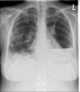

Infective emboli

Infective endocarditis is an infection of the inner surface of the heart, usually the valves. Symptoms may include fever, small areas of bleeding into the skin, heart murmur, feeling tired, and low red blood cell count. [Source: Wikipedia ]